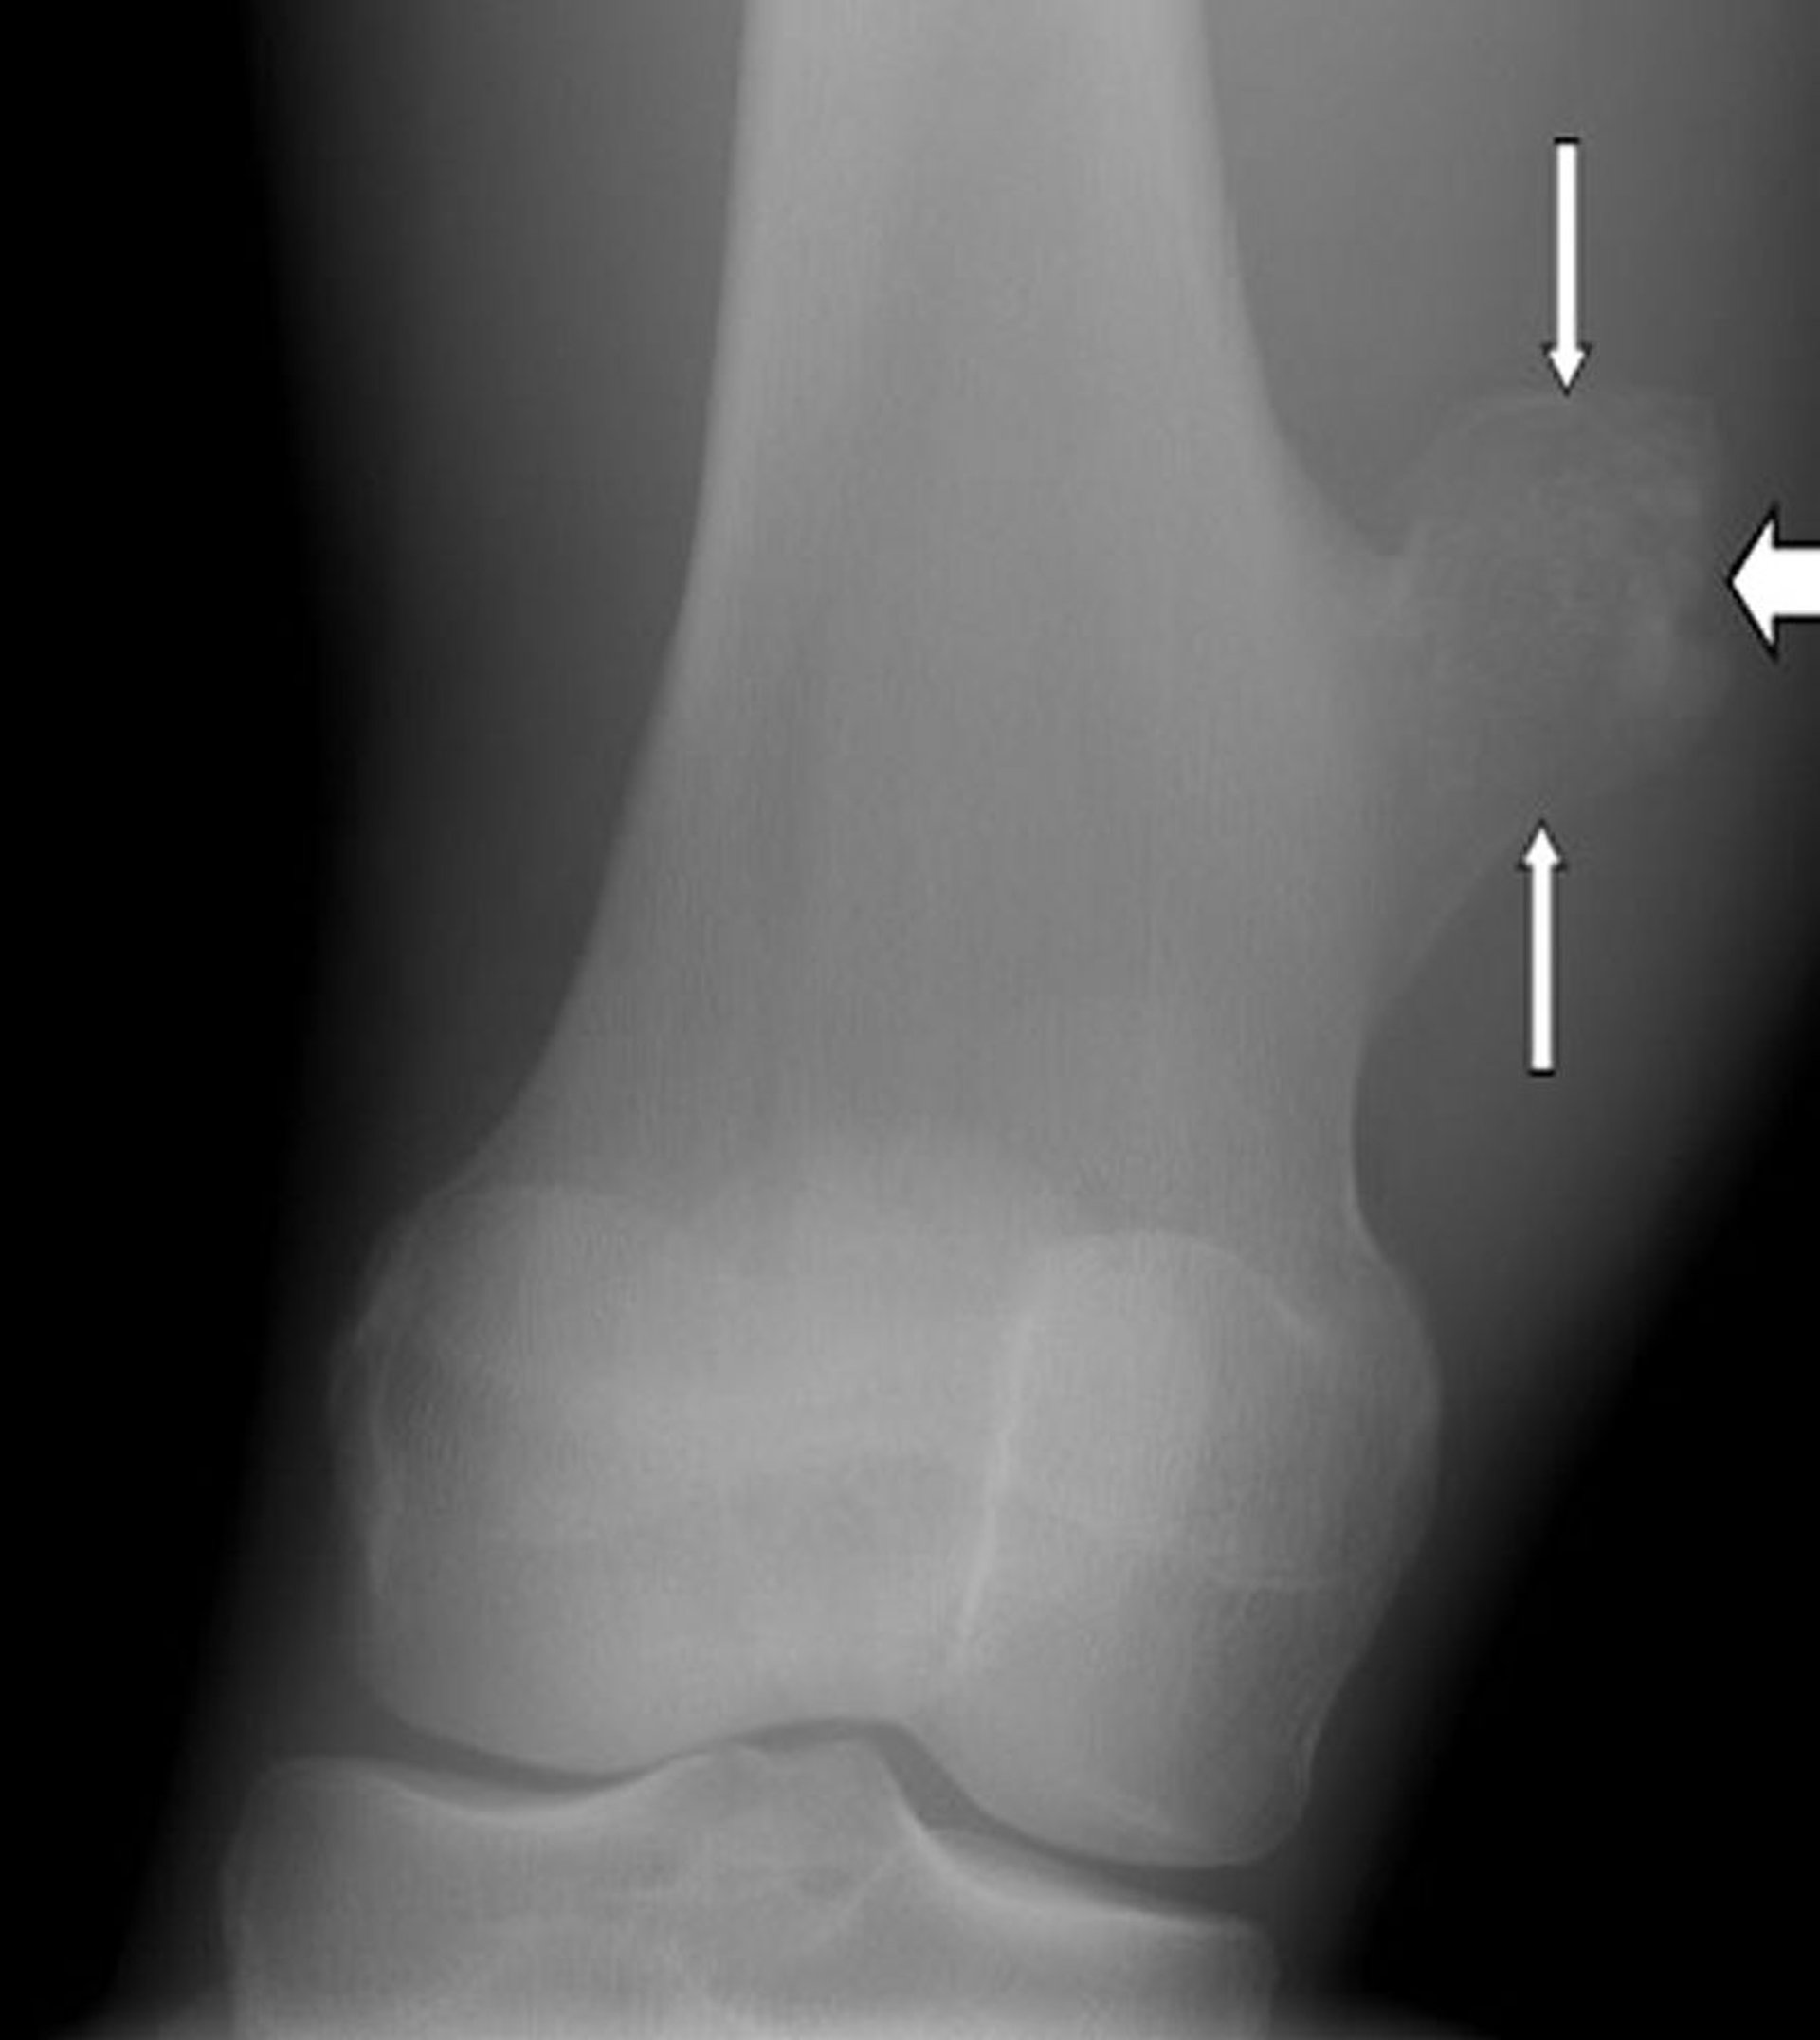

Esta radiografia do joelho mostra um osteocondroma, que é o crescimento na superfície do osso da coxa (setas) acima da articulação do joelho.